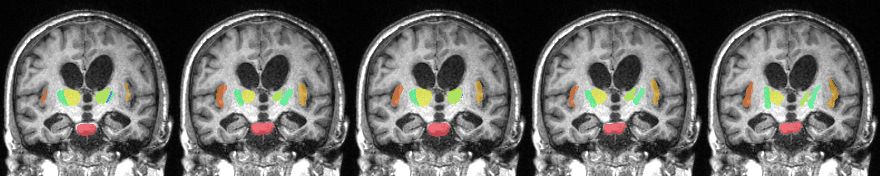

Segmentation Visualization

Left to Right: LT-Net, DeepAtlas, Brainstorm, Ours, and ground truth.